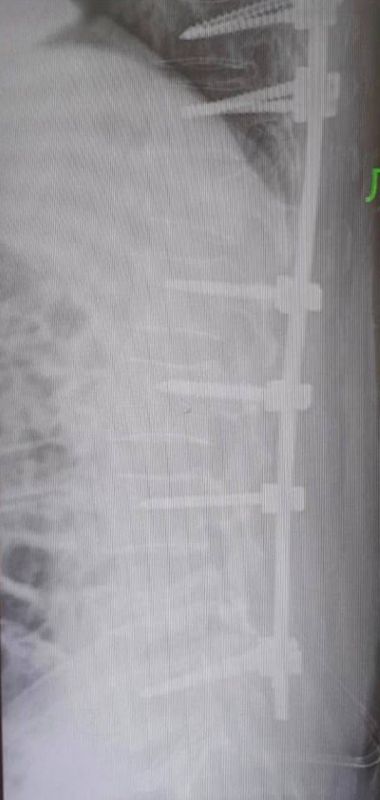

У пациента была очень тяжелая травма: компрессионно-оскольчатый перелом грудного и поясничного позвонков. В таком случае хребет разрушается из-за сильной нагрузки. Кости могут сдавить спинной мозг и нервные корешки.Нейрохирурги провели ювелирную и...